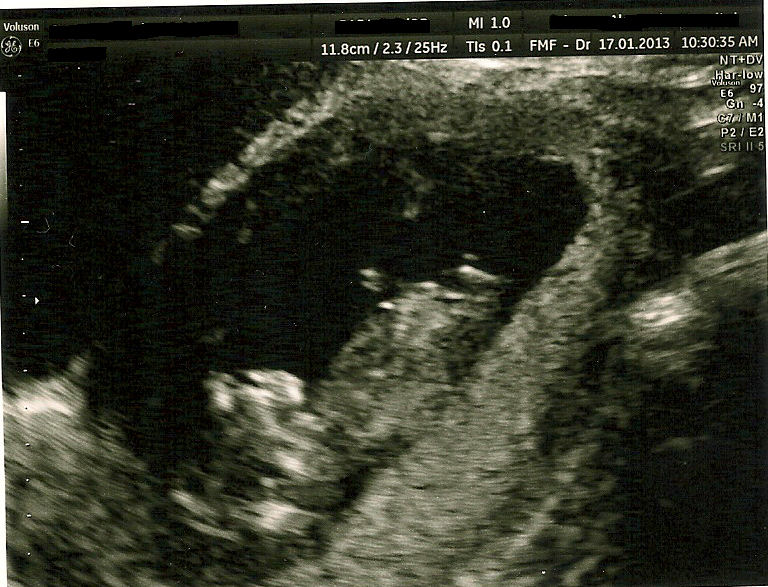

everythings good, perfect size etc.